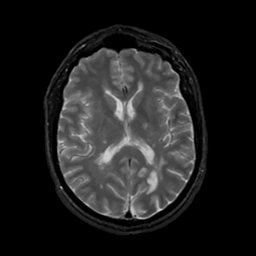

MR Study #4, March 3, 1991 -- Slice #28